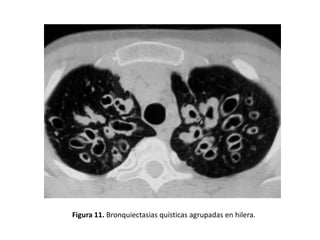

• Pueden verse imágenes aéreas con pared definida o

lesiones quísticas, con o sin nivel hidroaéreo (Figura

11)

Figura 11. Bronquiectasias quísticas agrupadas en hilera.

• Quísticas:

– Es la expresión más grave de la enfermedad.

– Los bronquios adquieren una forma sacular o de

quiste.

– Pueden presentar niveles hidroaéreos o estar

agrupadas en racimos o hileras.

– Adoptan la típica imagen de “nido de golondrina”

cuando el moco se acumula dentro de las lesiones y

aparece un nivel hidroaéreo (Figuras 11, 14, 15, 17, 21

y 25).

– Son frecuentes en la aspergilosis broncopulmonar

alérgica (ABPA) y en la fibrosis quística

• Los distintos tipos morfológicos se correlacionan

con la severidad de la enfermedad (las varicosas y

quísticas son manifestación de una enfermedad

más avanzada).

• Pacientes con BQ quísticas presentaban con más

frecuencia esputos purulentos, colonización por

Pseudomonas aeruginosa y mayor alteración de

los parámetros espirométricos que los pacientes

con BQ cilíndricas o varicosas.